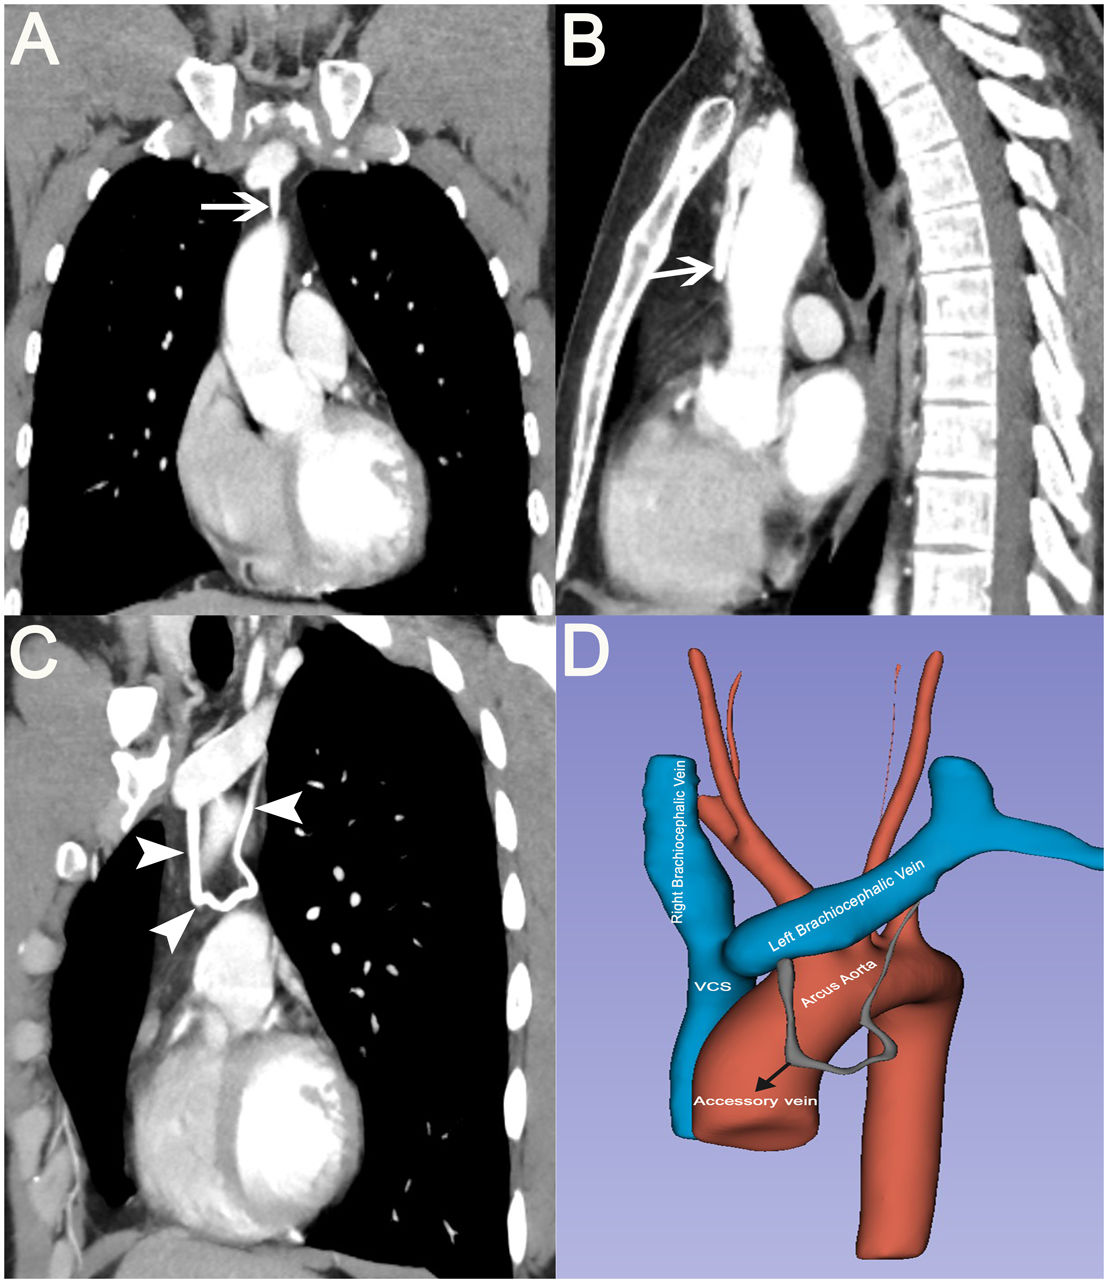

This report describes a 31-year-old asymptomatic man under surveillance for multiple pulmonary nodules. Contrast-enhanced computed tomography revealed an incidental 3.8-mm anomalous venous branch arising from the left brachiocephalic vein, coursing through the anterior mediastinum, forming a vascular ring, and subsequently draining back into the same vein (Fig. 1A–D). The exact cause of LBCV variations remains unknown. Chen et al. proposed the existence of 2 transverse channels in the early stages of embryonic development, initially positioned one above and the other below. These channels are interconnected by an intersubcardinal anastomosis, essentially forming a vascular network. Throughout time, the lower channel and vascular network regress, while the upper channel transforms into the left brachiocephalic vein [1]. In our case, we identified a rare vascular variant, a remnant of the vascular network from the embryonic development process. Although vascular anatomical variations are typically asymptomatic, they carry a higher risk of thrombosis due to gravitational pooling, making follow-up essential, especially in patients prone to thrombosis. Additionally, as mentioned in the case reports by Steckiewicz et al. the presence of a double LBCV may lead to complications during thoracic procedures, pacemaker implantation, and central venous catheterizations. Therefore, imaging is recommended before performing such procedures [1,2].

(A, B) Coronal and sagittal contrast-enhanced thoracic CT images showing an accessory vein originating from the left brachiocephalic vein and draining back into the same vein (arrows). (C) On the coronal maximum intensity projection (MIP) image, the entire course of the accessory vein is visualized (arrowheads). (D) Three-dimensional (3D) reconstruction image showing the normal vascular structures along with the accessory vein.